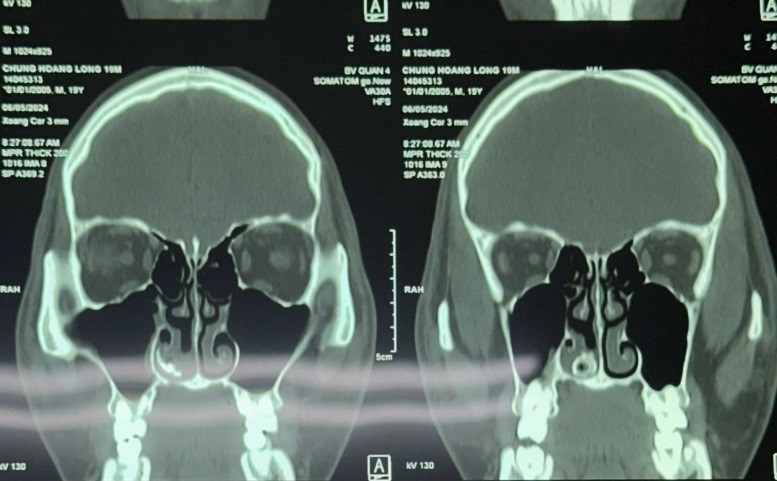

Bệnh nhân được chỉ định chụp CT scans và kết quả ghi nhận khối cản quang nghi ngờ dị vật trong hốc mũi bên phải.